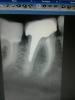

Денис481 Опубликовано 26 сентября, 2012 Автор Поделиться Опубликовано 26 сентября, 2012 вот и снимок Ссылка на комментарий

KIS Опубликовано 27 сентября, 2012 Поделиться Опубликовано 27 сентября, 2012 Вот и вкв! Ссылка на комментарий

Денис481 Опубликовано 27 сентября, 2012 Автор Поделиться Опубликовано 27 сентября, 2012 да да,есть оказывается Ссылка на комментарий